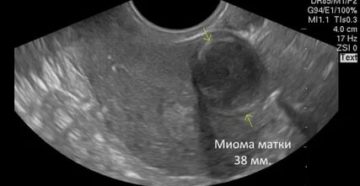

Миома матки: размеры в неделях и сантиметрах, причины, методы лечения, отзывы 16 Сентября, 2018 Акушерство…